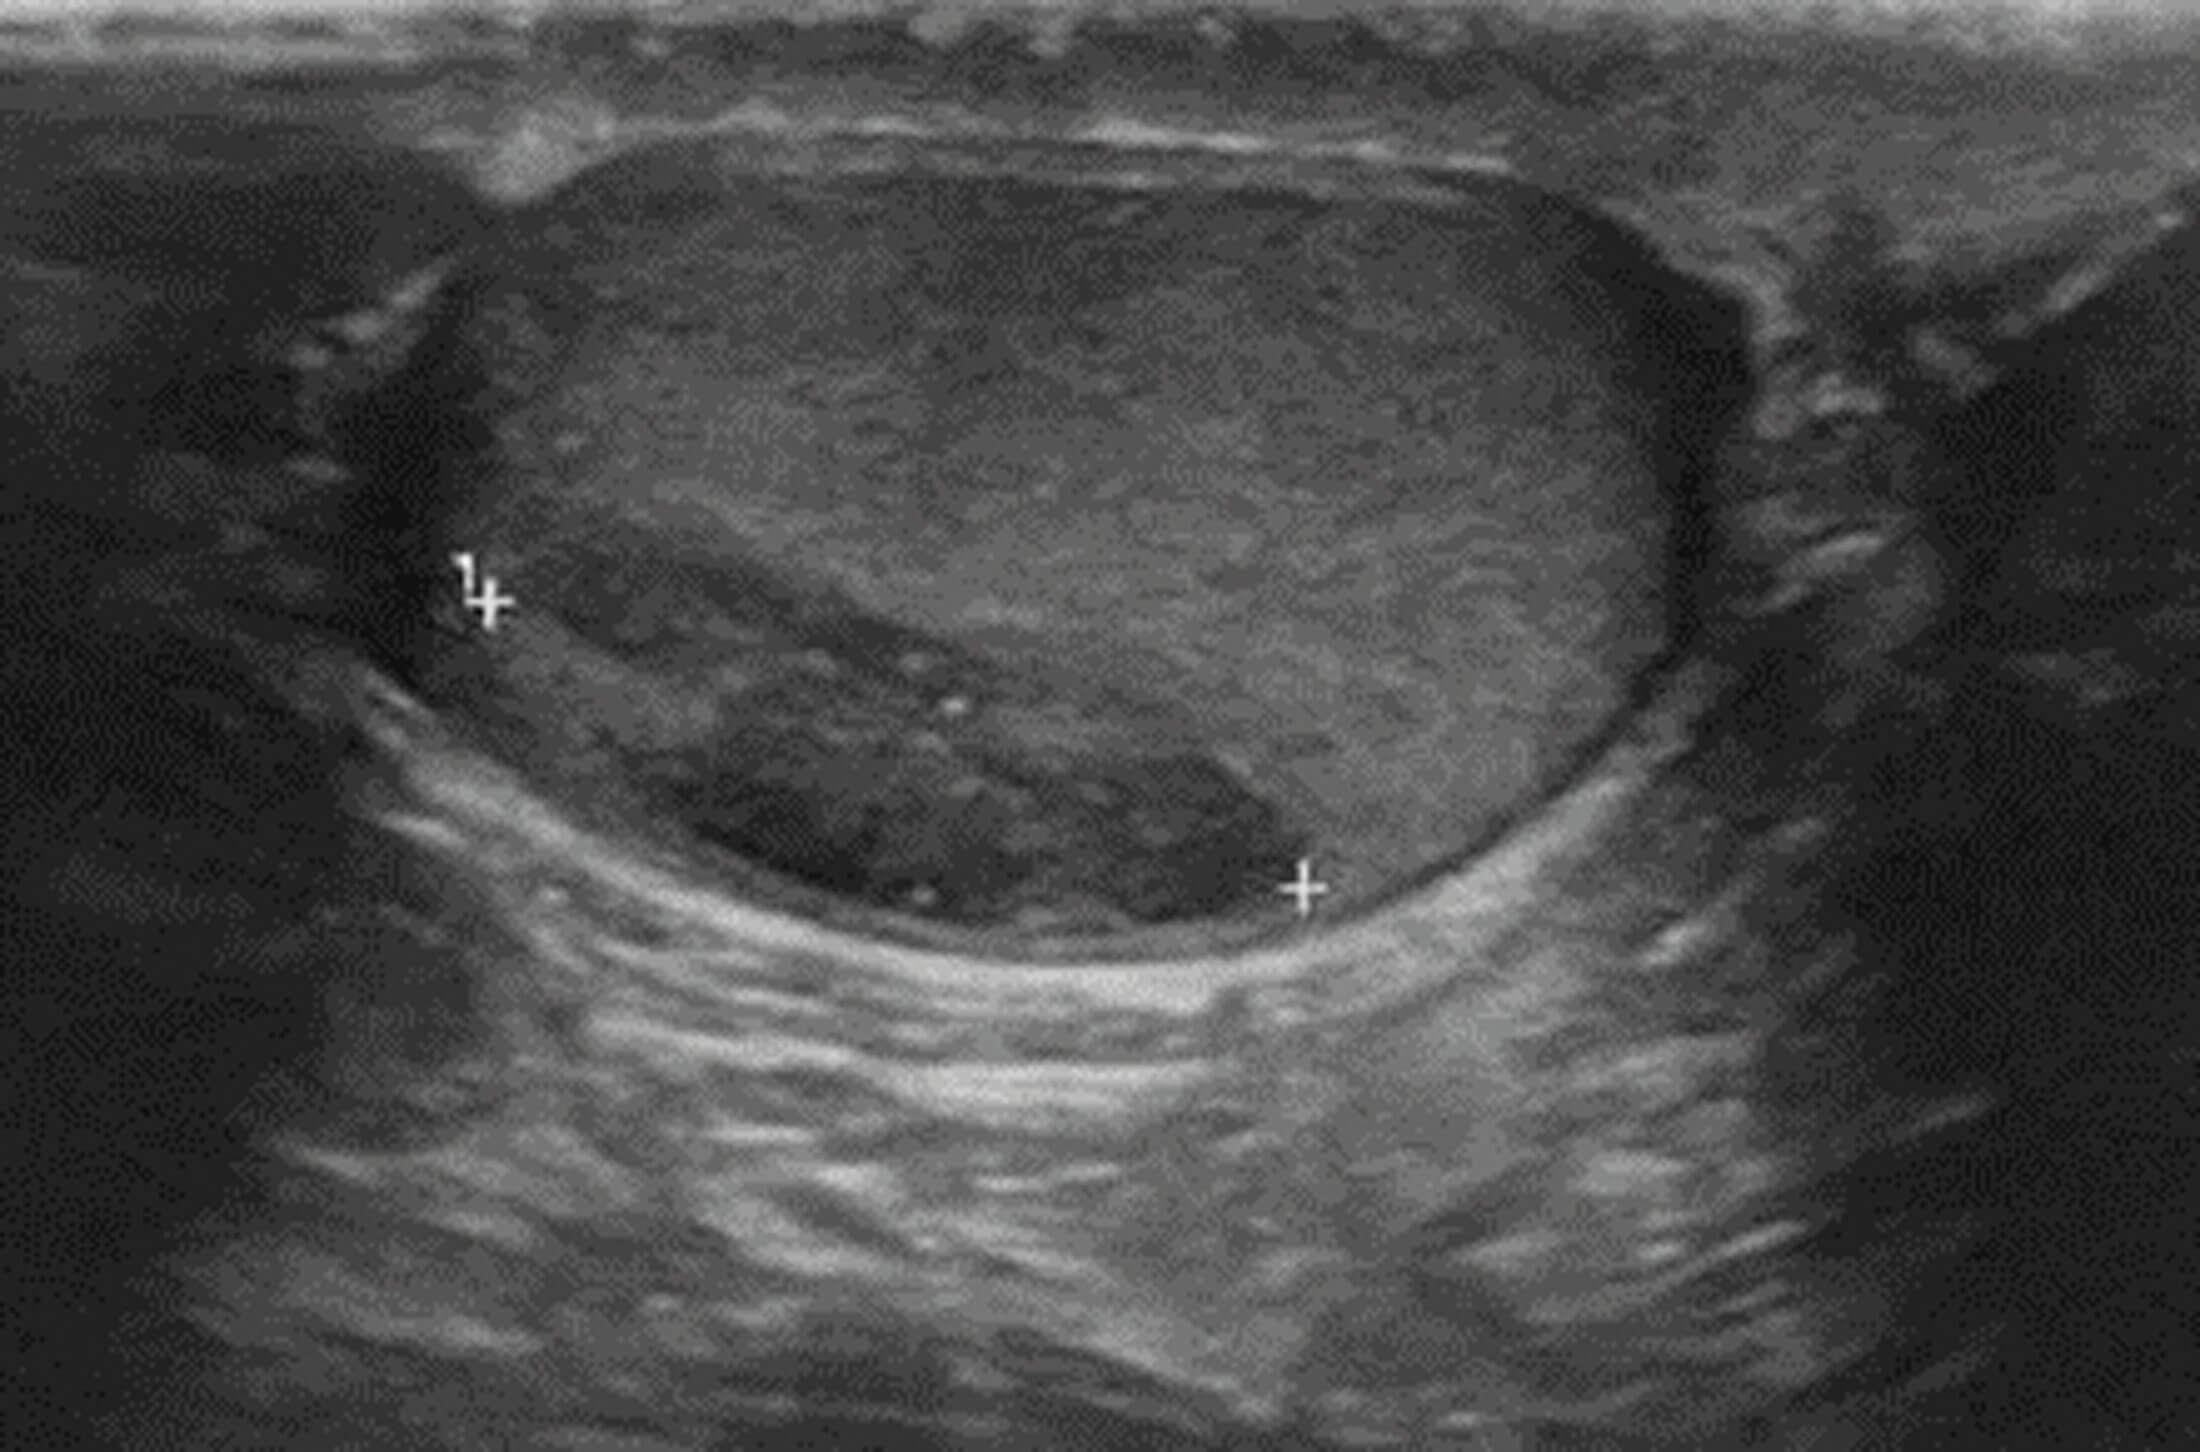

The patient was commenced on low molecular weight heparin and a CT-guided biopsy was performed - histology showed metastatic seminoma, and he was referred to the urology team. A subsequent US testes showed a 1.5cm right sided testicular lesion (Figure 2).

Figure 2: Lesion on the testicular midpole undersurface, with reduced reflectivity, classical for seminoma.